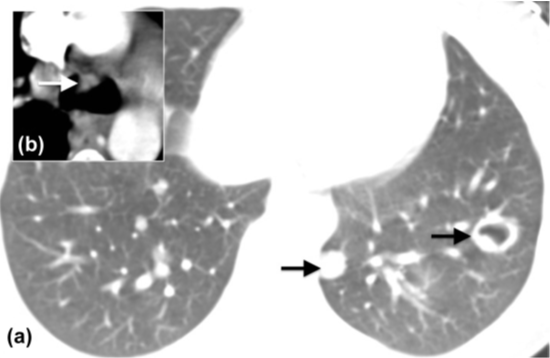

5. 良性肿瘤形成空洞较为少见,可见于气管支气管乳头状瘤,结节在腔内播散并形成空洞(图2)。

图2 气管乳头状瘤。(a)孤立性气管息肉(箭头)。(b)多发实性和空洞性肺结节(箭头)。

2. 曲菌球是在原有空洞基础上发生二重感染形成的,由菌丝、炎性细胞、纤维蛋白和碎片组成(图5)。曲菌球若边缘光滑,一侧与空洞壁之间形成新月形透亮区,称“空气新月征”。邻近胸膜增厚是一个早期征象,出现时间比曲菌球早3年左右。气液平面、空洞内完全填充及钙化较少见。无强化结节、附近有支扩、已有肺基础病变、随体位改变移动可作为与恶性空洞性病变的鉴别点。50%~80%的患者并发支气管动脉增粗,这可能引起致命性的大咯血(图5)。

图5 曲菌球形成。a)右肺上叶较大空洞(*),壁薄。(b)洞壁增厚,与腔内肿块(*)形成“空气新月征”,邻近胸膜增厚(箭头)。(c)2年后,成熟曲菌球形成,增粗的肋间动脉和支气管动脉间形成侧支循环(箭头),后经血管造影证实(d)。